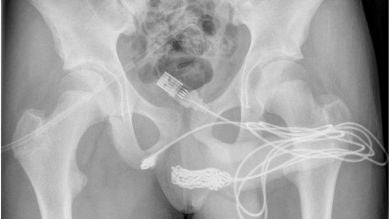

Intentó quitárselo él mismo, pero el cable USB se enredó aún más y los dos extremos quedaron colgando de su pene. Al final el joven tuvo que acudir a urgencias y terminó sometiéndose a una cirugía de emergencia para retirar el cable USB. Su caso fue detallado en el artículo, titulado "Autoinserción uretral de un cable USB como experimentación sexual: informe de un caso", que se publicó en la revista médica Urology Case Reports junto con las impactantes imágenes.

Los padres del adolescente se vieron obligados a llevarlo a la sala de emergencias después de que orinó sangre debido al cable USB atascado en su pene. El personal del hospital no pudo retirarlo al principio, por lo que transfirieron al niño al University College Hospital de Londres para que recibiera la cirugia necesaria.

Los médicos tuvieron que cortar el músculo bulboesponjoso, el área entre los genitales y el ano, para sacar el cable USB. Pero no pudieron pasar la parte anudada del cable a través de ese corte antes de sacar las piezas restantes del cable eléctrico. Afortunadamente, el niño no necesitó más tratamiento y fue dado de alta al día siguiente.